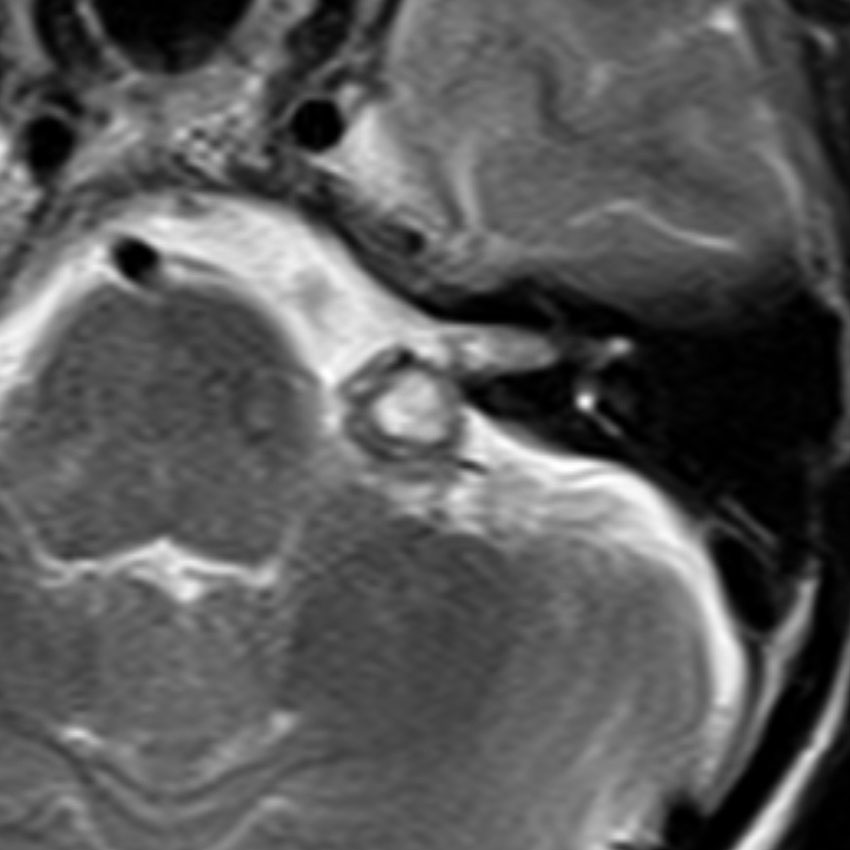

脳幹部の海綿状血管腫 brainstem cavernous hemangioma

2度の延髄内出血を生じた海綿状血管腫です。でも初回の出血からすでに27年間がたちます。症状も回復して麻痺もなくていまは社会生活に困ることはありません。脳幹部の海綿状血管腫の中には1ヶ月に何回もひどい出血を繰り返すのもあるのですが,この例のように30年近い間に軽い出血が2回だけというのもあります。残念ながら正確にこれを予測することはできません。この患者さんの海綿状血管腫は手術で摘出すれば麻痺などの合併症の可能性があるのでしません。

脳幹部の海綿状血管腫を手術した方がいいかどうかはすごく慎重に判断しないといけないのです。場合によってはとても重い後遺症が手術ででてしまうこともあります。もちろん手術ですごく症状がよくなってとても元気に暮らしている患者さんもたくさんいますが,そうでない患者さんもいるのです。手術を決意する前に,少なくとももう一人の脳外科医からセカンドオピニオンを聞きましょう。